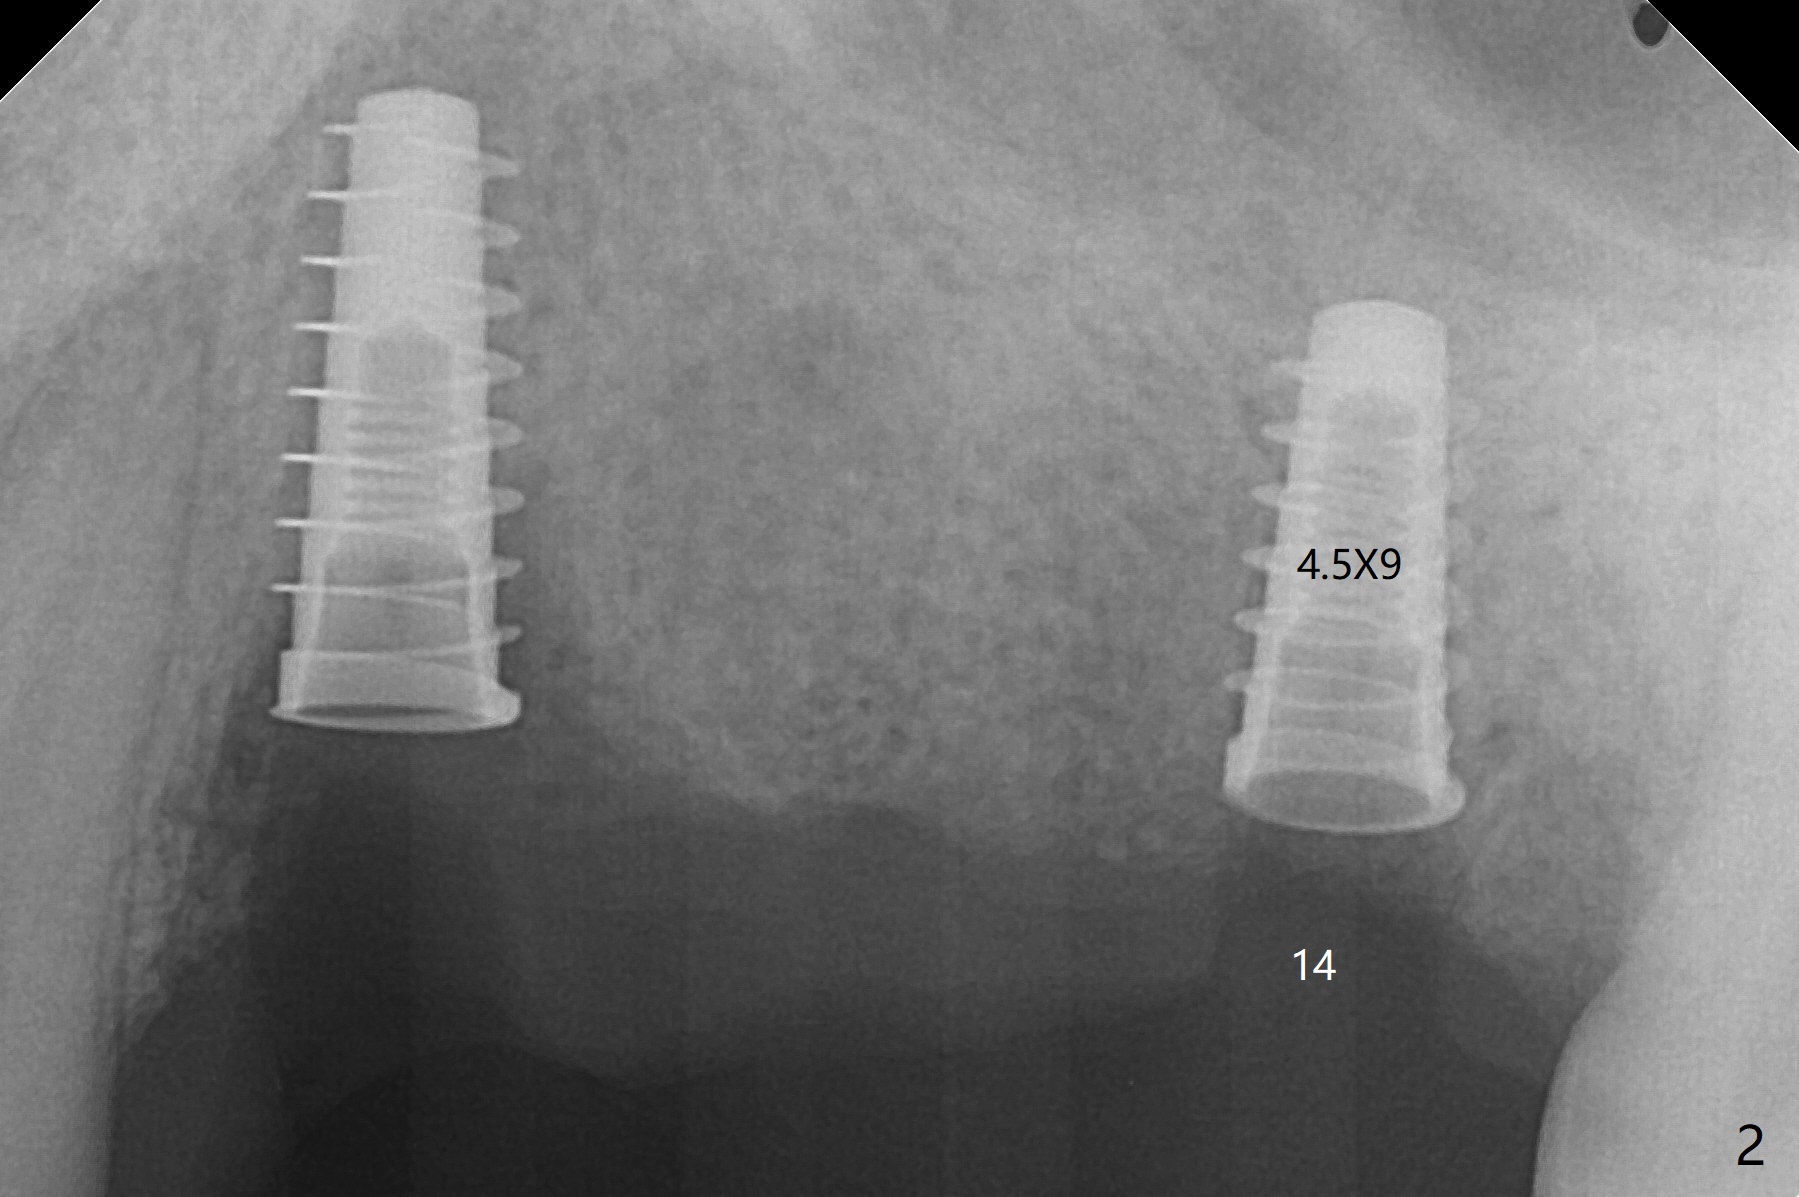

Immediate placement at #12 is smooth with 20 Ncm, whereas delayed one at #14 involves sinus membrane perforation; after insertion of PRF and mixture of autogenous bone and allograft, a shorter dummy implant tries in with stability (Fig.1). The final implant at #14 has ~60 Ncm, but the coronal palatal bone may be insuficient (Fig.2). Sticky bone is placed to bury the implant at #14 (Fig.3 *). After placement (incomplete, Fig.3 <) of a 4.5x7.5(4) mm pair abutment, setting acrylic is applied around the abutment, over the bone graft at #14 (to prevent loss) and pressed into the undercuts of the proximal surfaces of the neighboring teeth for retention (Fig.4). The sockets at #12 heals 8 days postop when a 2nd acrylic dressing dislodges (Fig.5). It appears that the retention of 3-unit acrylic dressing is poor. The wound at #14 also heals, but it would be better to make an incision to save the soft tissue (Fig.6). The bone/implant gap reduces at #13 five months postop (Fig.7 (complete abutment seating)). There is no implant thread exposure at #13 (immediate), while minor exposure mesial to #15 (delayed). The patient complains of food impaction between #13 and 14 buccally 6 months post cementation (Fig.8). Return to Upper Molar Immediate Implant, No Deviation 19 Next Case Xin Wei, DDS, PhD, MS 1st edition 01/21/2020, last revision 02/03/2021